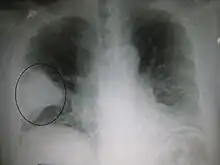

Nodule

A lung nodule is a discrete opacity in the lung which may be caused by:

- Neoplasm: benign or malignant

- Granuloma: tuberculosis

- Infection: round pneumonia

- Vascular: infarct, varix, granulomatosis with polyangiitis, rheumatoid arthritis

There are a number of features that are helpful in suggesting the diagnosis:

- rate of growth

- Doubling time of less than one month: sarcoma/infection/infarction/vascular

- Doubling time of six to 18 months: benign tumor/malignant granuloma

- Doubling time of more than 24 months: benign nodule neoplasm

- calcification

- margin

- smooth

- lobulated

- presence of a corona radiata

- shape

- site

If the nodules are multiple, the differential is then smaller:

- infection: tuberculosis, fungal infection, septic emboli

- neoplasm: e.g., metastases, lymphoma, hamartoma

- sarcoidosis

- alveolitis

- auto-immune disease: e.g., granulomatosis with polyangiitis, rheumatoid arthritis

- inhalation (e.g., pneumoconiosis)

Cavities

A cavity is a walled hollow structure within the lungs. Diagnosis is aided by noting:

- wall thickness

- wall outline

- changes in the surrounding lung

The causes include:

- cancer

- infarct (usually from a pulmonary embolus)

- infection: e.g., Staphylococcus aureus, tuberculosis, Gram negative bacteria (especially Klebsiella pneumoniae), anaerobic bacteria, and fungus

- Granulomatosis with polyangiitis